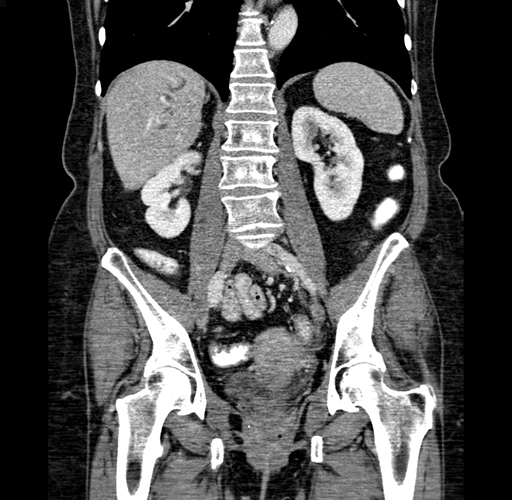

Pre-Chemo: Coronal Venous

Coronal Venous